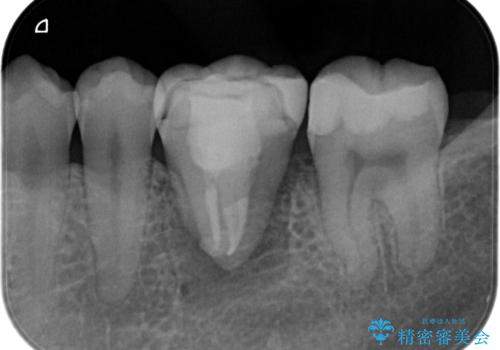

- 銀歯の下が大きな虫歯になり、保存困難のためその後の治療計画について悩まれていた患者様です。

選択肢としては、

①入れ歯、②ブリッジ、③インプラント、④歯牙移植

があります。

患者様と相談し、親知らずを用いて歯牙移植を行いました。